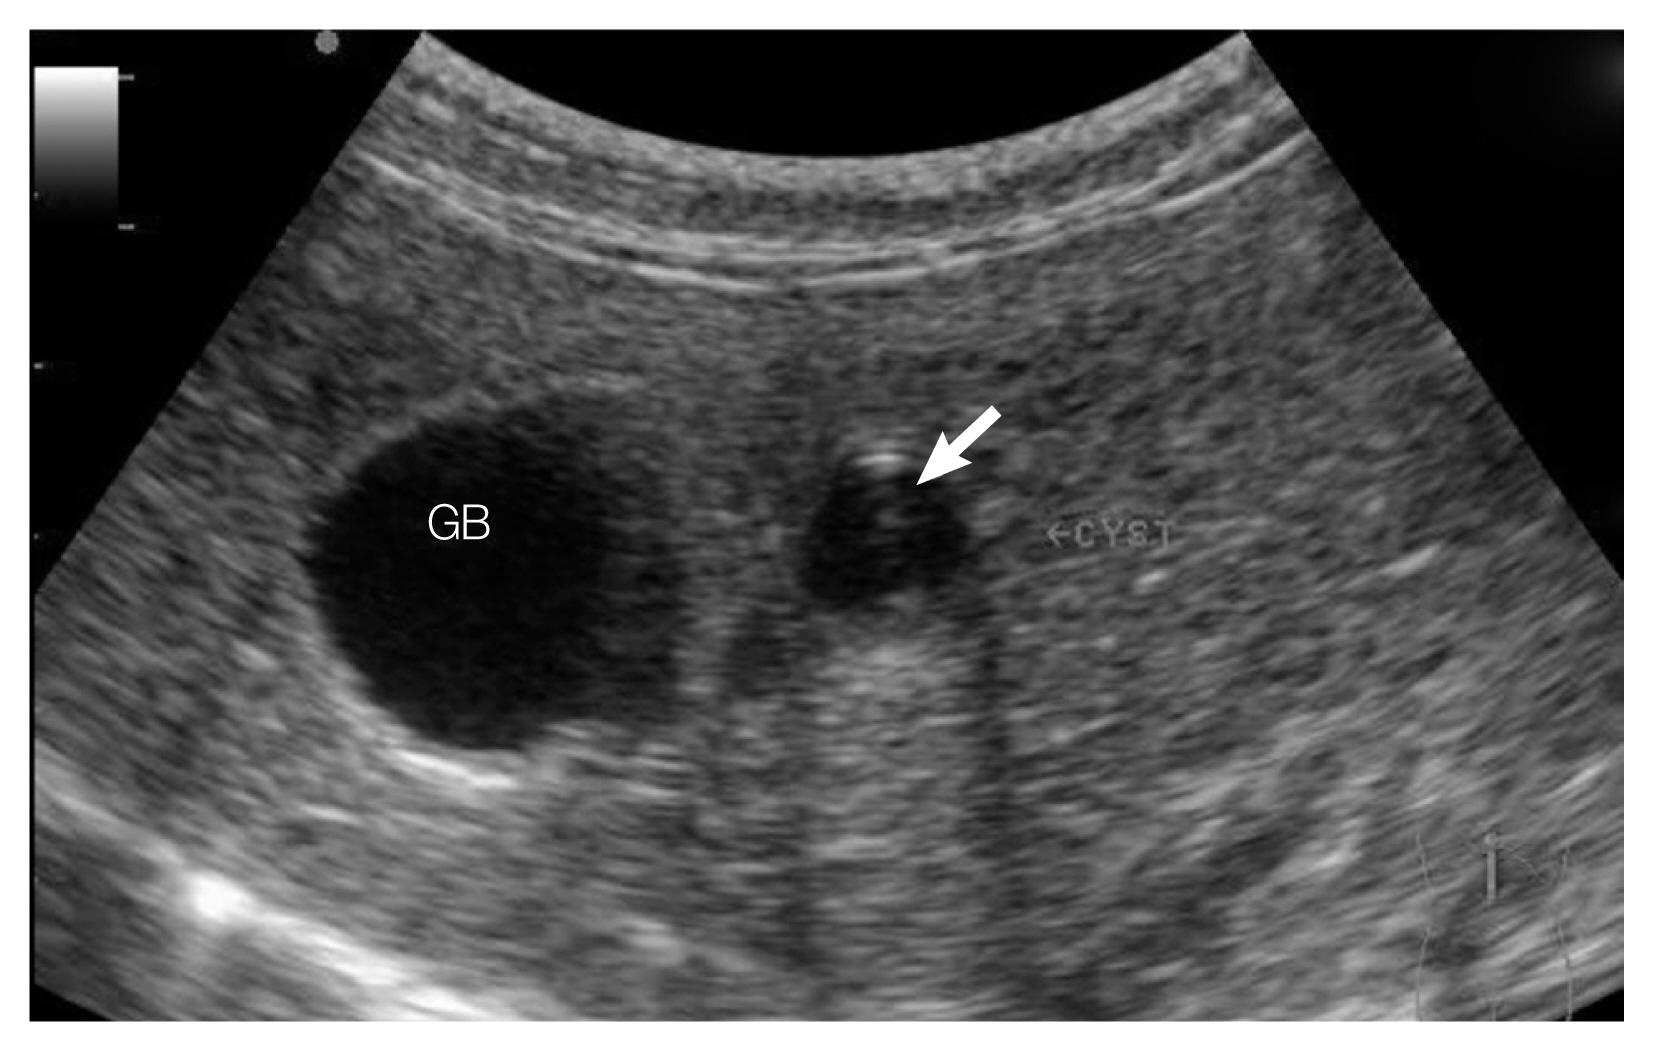

A leopard cat was introduced from Gyeongsangnam-do Forest Environment Research Institute, Jinju-si (city), Gyeongsangnam-do (province) to Cheongju Zoo, in Cheongju-si, Chungcheongbuk-do, Korea in August 2014. The cat was adult female, 3.26 kg in weight. It was known as a captive animal which was rescued from wild habitat in Gyeongsangnam-do but the exact locality was unknown. During the introduction process, chicken meat was given daily and mice were fed in a week but, no fishes were given. Vaccines and parasiticides had not been administered. For quarantine and health check-up, zolazepam-tiletamine (Zoletile 50, Virbac Laboratories, Carros, France) 10 mg/kg and medetomidine (Domitor; Zoetis, Florham Park, New Jersey) 0.1 mg/kg were intramuscularly administrated and blood samples were collected from jugular vein. Then, general physical examination was performed, and blood chemistry was analyzed. The body condition of cat was comparatively good and not shown any typical symptoms with normal blood chemistry values except anorexia. Fecal examination using direct smear method resulted as negative for parasites. Additionally, abdominal ultrasonography was conducted because of the anorexia. At the ultrasonography imaging, cyst-like bile duct dilatation was observed nearly gall bladder. Echogenicity of walls of gall bladder and dilated bile duct were seemed slightly increased, and floating or deposited echogenic foci were detected from there.

Ultrasound-guided needle biopsy was performed for diagnosis the bile duct dilatation and identity of the echogenic foci (Fig. 1). Few millimeters of Bile juice with the debris were collected and observed under light microscopy on the slide glass with cover slip. Numerous parasite eggs were observed (Fig. 2). The eggs were 25–33 (28±3) μm by 18–22 (20±1) μm in size, and they equipped with a dominantly developed small operculum, shoulder rim, dust-like wrinkles in surface and a miracidium inside. Observed parasite materials were deposited in the Parasite Resource Bank of Korea (PRB no. PRB001007). It was suggested that the cat infected with C. sinensis by the ultrasonographic findings, detection site of eggs and egg morphologies. To treat the liver fluke infection, 20 mg/kg of praziquantel (Distocide®, Shinpoong Pharm. Co., Seoul, Korea) was orally administered only once to the case. Follow-up studies including regular fecal examinations were conducted during 2 years after the treatment. And no more liver fluke eggs were detected after the treatment, and she still maintained good health condition.

The main tools for detecting clonorchiasis in our case were both of ultrasonography and ulatrasound-guided needle biopsy of bile juice. In the ultrasonogram, several findings which like bile duct dilation, floating echogenic foci in gall bladder, increased echogenicity of gall bladder wall and hepatobiliary tract were detected. These findings are very similar with the signs which detected from active clonorchiasis in human by ultrasonography. Ultrasonogram conducted on heavy infected cats by O. viverrini and P. fatosum also showed quite similar results with humans and our case [6,7]. These feautres are known to reflect periductal fibrosis with worm body and exudates of liver flukes in biliary system [3–7]. These pathological changes are not easy to detect in light or early infection cases by ultrasonography [3,4]. Thus, the patient might be infected with C. sinensis a long while ago.

Ultrasonography could be a useful indirect diagnostic tool for primary detection of clonorchiasis. Even in our case ultrasonography acted as additional filter for the detection although eggs of C. sinensis was not found at fecal examination. Indisciplined inspectors could miss the infection of C. sinensis due to its small size of the fluke ova. In addition, we used direct smear method for primal fecal examination. It could be a reason of the negative result.